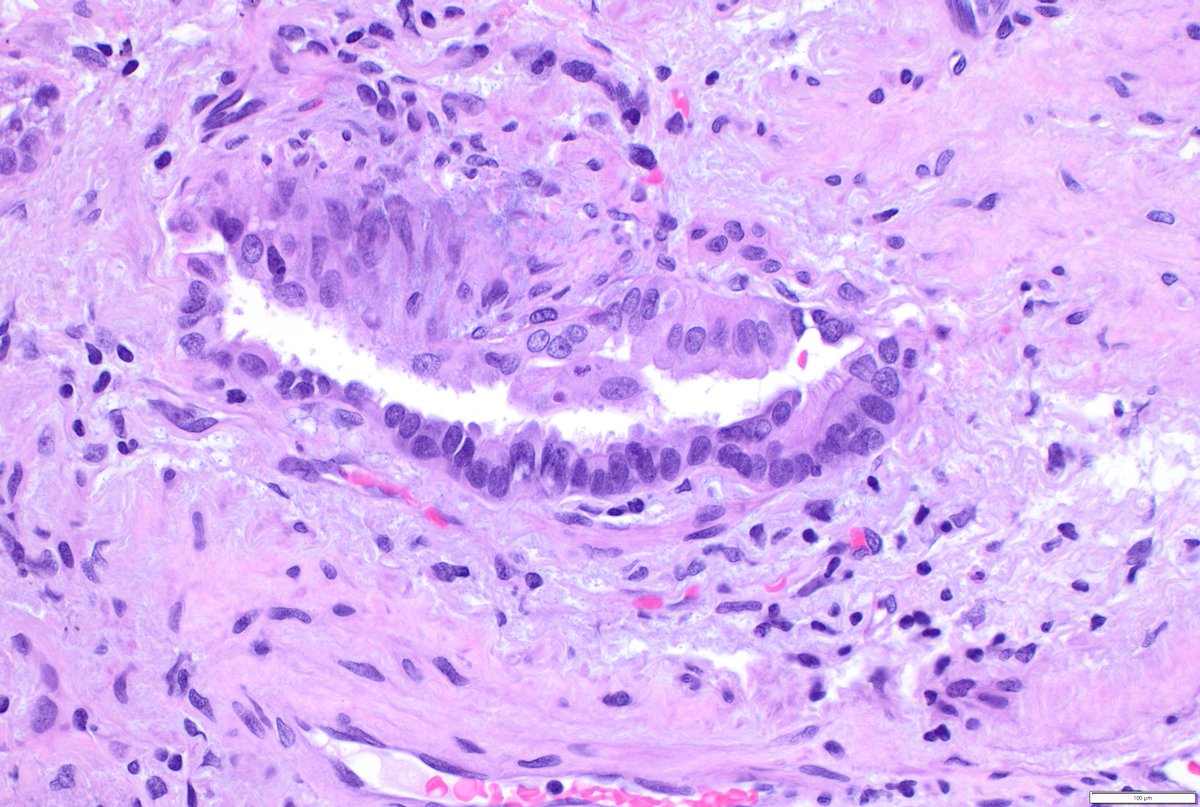

Just out in AJSP – a paper from our group describing a MAJOR new oddity. Tumors that normally arise in the jaw from tooth🦷precursors (ameloblastoma) – but as lung primaries 🫁! This was a neat collaboration b/w MSKCC, Mayo and UTSW where these cases were encountered independently, and we put our heads together with the help of original contributors and fellows to tackle this puzzle. Time will tell if these are truly exceptional or have been underrecognized. journals.lww.com/ajsp/fulltext/… @JLHornick @ENTpathology @MSKPathology @PulmPathSoc @yro854 @thoracicpath @Path_Matt @SansanoValero @AndreMo77438628